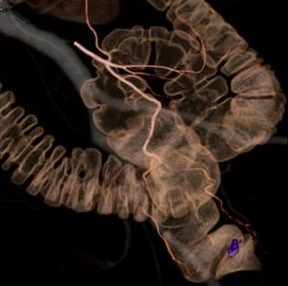

当院では、基本的に全手術症例に対し、3D-CT画像を術前シミュレーションと術中ナ

ビゲーションに活用して「腹腔鏡下結腸・直腸手術」をより安全で的確に行うようにし

ております。